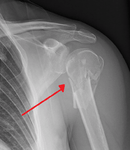

The head (caput humeri), is nearly hemispherical in form. It is directed upward, medialward, and a little backward, and articulates with the glenoid cavity of the scapula to form the glenohumeral joint (shoulder joint). The circumference of its articular surface is slightly constricted and is termed the anatomical neck, in contradistinction to a constriction below the tubercles called the surgical neck which is frequently the seat of fracture. Fracture of the anatomical neck rarely occurs.[1] The diameter of the humeral head is generally larger in men than in women.

Surgical neck

The surgical neck is a narrow area distal to the tubercles that is a common site of fracture. It makes contact with the axillary nerve and the posterior humeral circumflex artery.